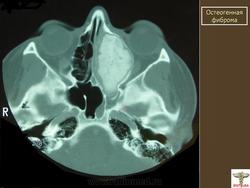

Фиброма остеогенная.

Фиброма остеогенная